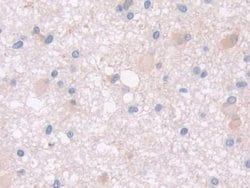

PON2 Polyclonal Antibody for Western Blot, IHC (P)

This gene encodes a member of the paraoxonase gene family, which includes three known members located adjacent to each other on the long arm of chromosome 7. The encoded protein is ubiquitously expressed in human tissues, membrane-bound, and may act as a cellular antioxidant, protecting cells from oxidative stress. Hydrolytic activity against acylhomoserine lactones, important bacterial quorum-sensing mediators, suggests the encoded protein may also play a role in defense responses to pathogenic bacteria. Mutations in this gene may be associated with vascular disease and a number of quantitative phenotypes related to diabetes. Alternatively spliced transcript variants encoding different isoforms have been described.Specifications

| Immunohistochemistry (Paraffin), Western Blot | |